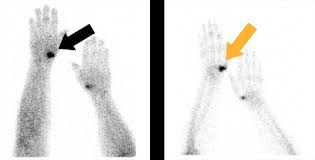

Vetmeduni Vienna Scintivet Informationsblatt Fur Pferdebesitzer

Vetmeduni Vienna Scintivet Informationsblatt Fur Pferdebesitzer from www.vetmeduni.ac.at

So können die wächterlymphknoten ausfindig gemacht und anschließend operativ entfernt werden, was. Mithilfe der szintigraphie lässt sich der lymphabfluss in der umgebung von tumoren darstellen. Je nach gewebeart, die untersucht werden soll, dauert die untersuchung 10 minuten bis eine stunde. Das dabei nach gabe eines radiopharmakons mit organspezifischer verteilung entstandene bild nennt man szintigramm. Szintigraphie — scintigrafija statusas t sritis standartizacija ir metrologija apibrėžtis junginių buvimo ir judėjimo gyvo organizmo organuose tyrimo būdas, pagrįstas žymėtųjų atomų stebėjimu.